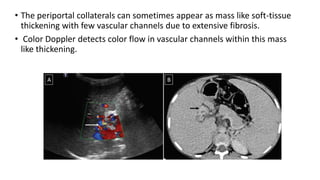

• The periportal collaterals can sometimes appear as mass like soft-tissue

thickening with few vascular channels due to extensive fibrosis.

• Color Doppler detects color flow in vascular channels within this mass

like thickening.